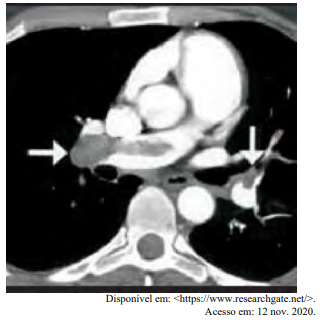

Certa idosa de 70 anos de idade é levada ao consultório médico por familiares, com relato de dor no peito há oito horas. Quanto a comorbidades, ela apresenta hipertensão arterial sistêmica e insuficiência cardíaca. Estava em casa assistindo à televisão quando sentiu uma dor súbita no peito, de moderada intensidade, que piora com a inspiração profunda, irradiando para o dorso, em queimação e associada a palpitações e a falta de ar importante, mesmo em repouso. Nega náuseas e sudorese. Não melhora após tomar dipirona. A dor continua da mesma forma, mas o que levou os familiares a procurarem atendimento foi a piora da falta de ar. Faz uso de losartana, atenolol, espironolactona, AAS e sinvastatina. Nega etilismo e informa que tinha o hábito de tabagismo, mas parou há mais de 10 anos. Tem histórico anterior de cirurgia de artroplastia de quadril há mais de um ano. Tem ficado muito tempo em repouso, assistindo à TV, principalmente depois da pandemia de Covid-19. Ao exame físico, constatam-se PA = 89 mmHg x 59 mmHg, FC = 125 bpm, FR = 27 ipm e SatO2 = 89% em ar ambiente. A paciente está afebril, em estado geral regular, lúcida, orientada e comunicativa. As auscultas pulmonar e cardíaca mostram-se sem alterações. Observam-se abdome inocente, membros inferiores com cacifo + discreto e simétrico, panturrilhas livres e pulsos preservados. A paciente realiza o eletrocardiograma e a tomografia de tórax, conforme representado nas imagens a seguir.

Com base nesse caso clínico, nos exames representados nas imagens e nos conhecimentos médicos correlatos, julgue o item a seguir.

O médico assistente calculou o escore de Wells e o resultado foi de 7. Nesse momento, o próximo passo mais indicado é solicitar dímero d, pois a paciente apresenta alta probabilidade de TEP.